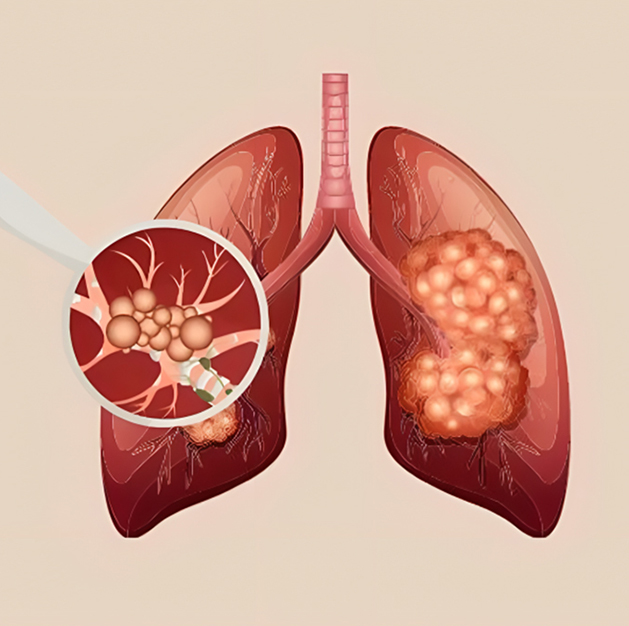

Interstitial Lung Diseases (ILD)